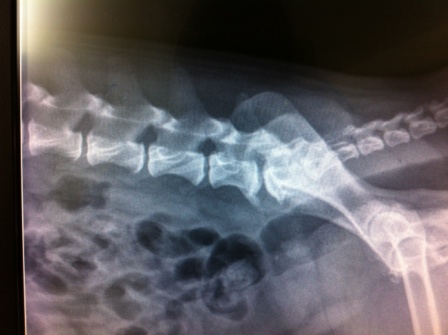

– la radiografía no revela nada al nivel urogenital, pero observamos una cierta reorganización al nivel del espacio lombo-consagrado y un sacro que parece estar en flexión.